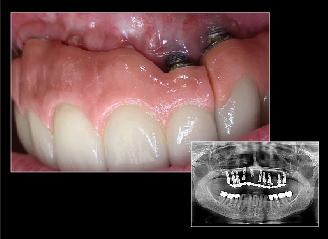

Fig 13. COCO Lux is used here for emergency treatment, blunt force trauma to the right lateral incisor.

Figure 13

Fig 14. Specialist referrals can also be aided by clear photographs. In this case, an image captured using COCO Lux shows the exposure of implant threads and ulcerations under the prosthesis at 2 years.

Figure 14